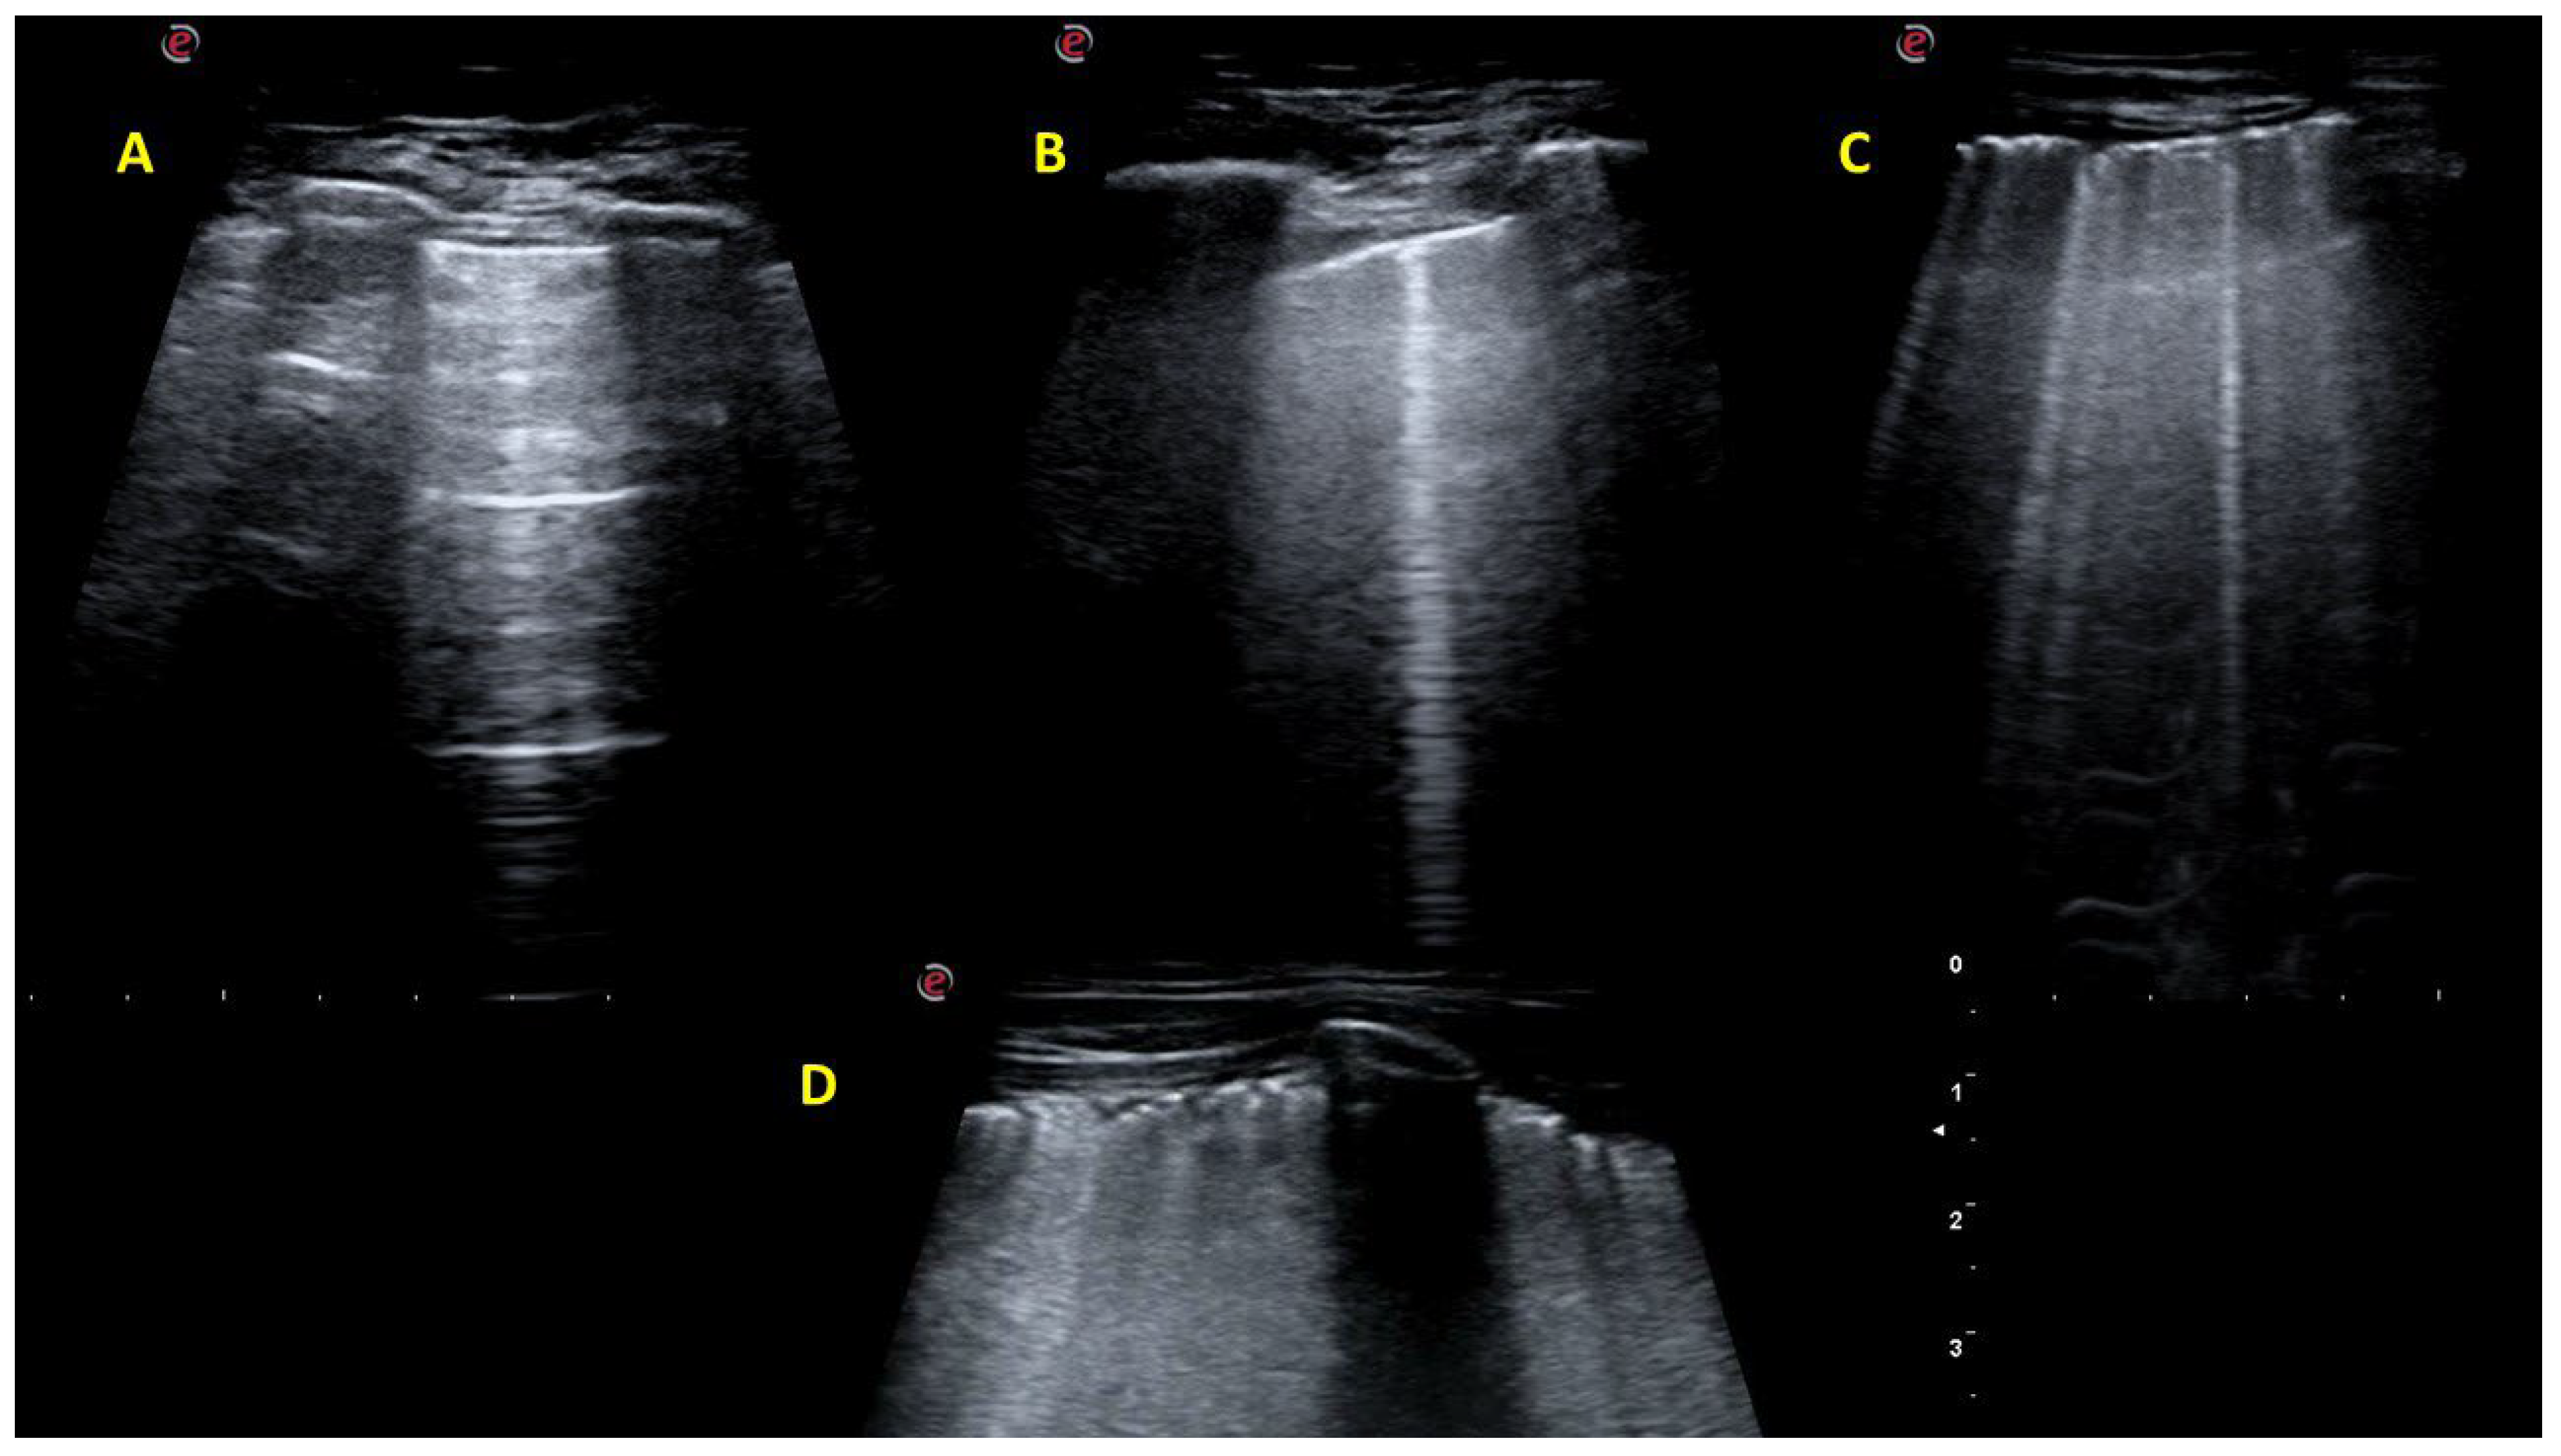

2.2. Lung Ultrasound Investigation